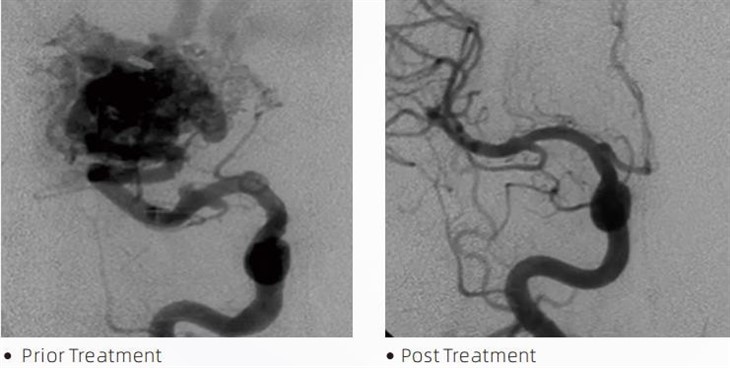

ΛάβαΥΔΗ εμβολική κόλλα είναι μια ιατρική συσκευή που χρησιμοποιείται από επεμβατικούς νευροακτινολόγους κατά τη διάρκεια ελάχιστα επεμβατικών διαδικασιών για τη θεραπεία καταστάσεων όπως εγκεφαλικά ανευρύσματα, αρτηριοφλεβικές δυσπλασίες και όγκους. Η εμβολική κόλλα Lava προσφέρει πολλαπλά οφέλη τόσο στους επαγγελματίες του ιατρικού τομέα όσο και στους ασθενείς όσον αφορά την ασφάλεια, την ευκολία χρήσης και την αποτελεσματικότητα. Η λάβα είναι σε θέση να σφραγίζει τα αιμοφόρα αγγεία γρήγορα και αποτελεσματικά. Η διαδικασία περιλαμβάνει την έγχυση της κόλλας απευθείας στο στοχευόμενο αγγείο, όπου πολυμερίζεται και σκληραίνει σε μια μάζα που μοιάζει με χυτό που γεμίζει το ανεύρυσμα ή τη δυσπλασία. Στη συνέχεια διακόπτει αποτελεσματικά τη ροή του αίματος στη βλάβη, αποτρέποντας τη ρήξη της και μειώνοντας τον κίνδυνο μόνιμης βλάβης ή εγκεφαλικού. Η λάβα περιλαμβάνει τη λάβα-12, τη λάβα-18 και τη λάβα-34. Κάθε σύνθεση έχει σχεδιαστεί για να καλύπτει συγκεκριμένες κλινικές ανάγκες. Η Lava-18 είναι τυπική σύνθεση για γενική χρήση. Η Lava-34 είναι κόλλα υψηλού ιξώδους για δοχεία υψηλής ροής. Ενώ η λάβα-12 έχει χαμηλότερο ιξώδες και είναι πιο ρέουσα, επιτρέποντας απομακρυσμένα μικροαγγεία. Με αυτές τις επιλογές, οι επεμβατικοί νευροακτινολόγοι μπορούν να επιλέξουν τα κατάλληλα σκευάσματα Lava για να εξασφαλίσουν τα βέλτιστα αποτελέσματα. Ένα από τα πιο αξιοσημείωτα χαρακτηριστικά της λάβας είναι οι μη κολλητικές της ιδιότητες. Αυτή η ουσία είναι ειδικά σχεδιασμένη για να παραμένει σταθερή μέχρι να φτάσει στην περιοχή στόχο. Αυτό το χαρακτηριστικό σημαίνει ότι η εμβολική κόλλα Lava μπορεί να τοποθετηθεί με ακρίβεια μέσα στην αρτηρία και να παραμείνει εκεί χωρίς να κολλήσει ή να κολλήσει στον περιβάλλοντα ιστό.